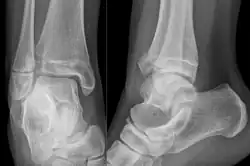

There are three x-ray views in a complete ankle series: anteroposterior (AP), lateral, and oblique (or "mortise view"). The mortise view is an AP x-ray taken with the ankle internally rotated 15-20 degrees since the foot is naturally externally rotated relative to the ankle.[9] In addition to these views, a full-length view of the tibia and fibula may be necessary to evaluate for injuries to the proximal fibula associated with Maisonneuve fractures.

On X-rays, there can be a fracture of the medial malleolus, the lateral malleolus, and/or of the anterior/posterior margin of the distal tibia. The posterior margin (known as the posterior malleolus) is much more frequently injured than the anterior aspect of the distal tibia. If both the lateral and medial malleoli are broken, this is called a bimalleolar fracture (some of them are called Pott's fractures). If the posterior malleolus is also fractured, this is called a trimalleolar fracture.